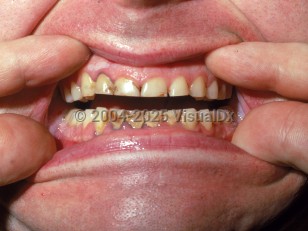

Lead poisoning

Clinical presentations are variable and dependent on patient age and severity of poisoning, but they generally include peripheral neuropathy, encephalopathy, anorexia, albuminuria, anemia, headache, hypertension, insomnia, irritability, tremor, weight loss, and gastrointestinal symptoms.